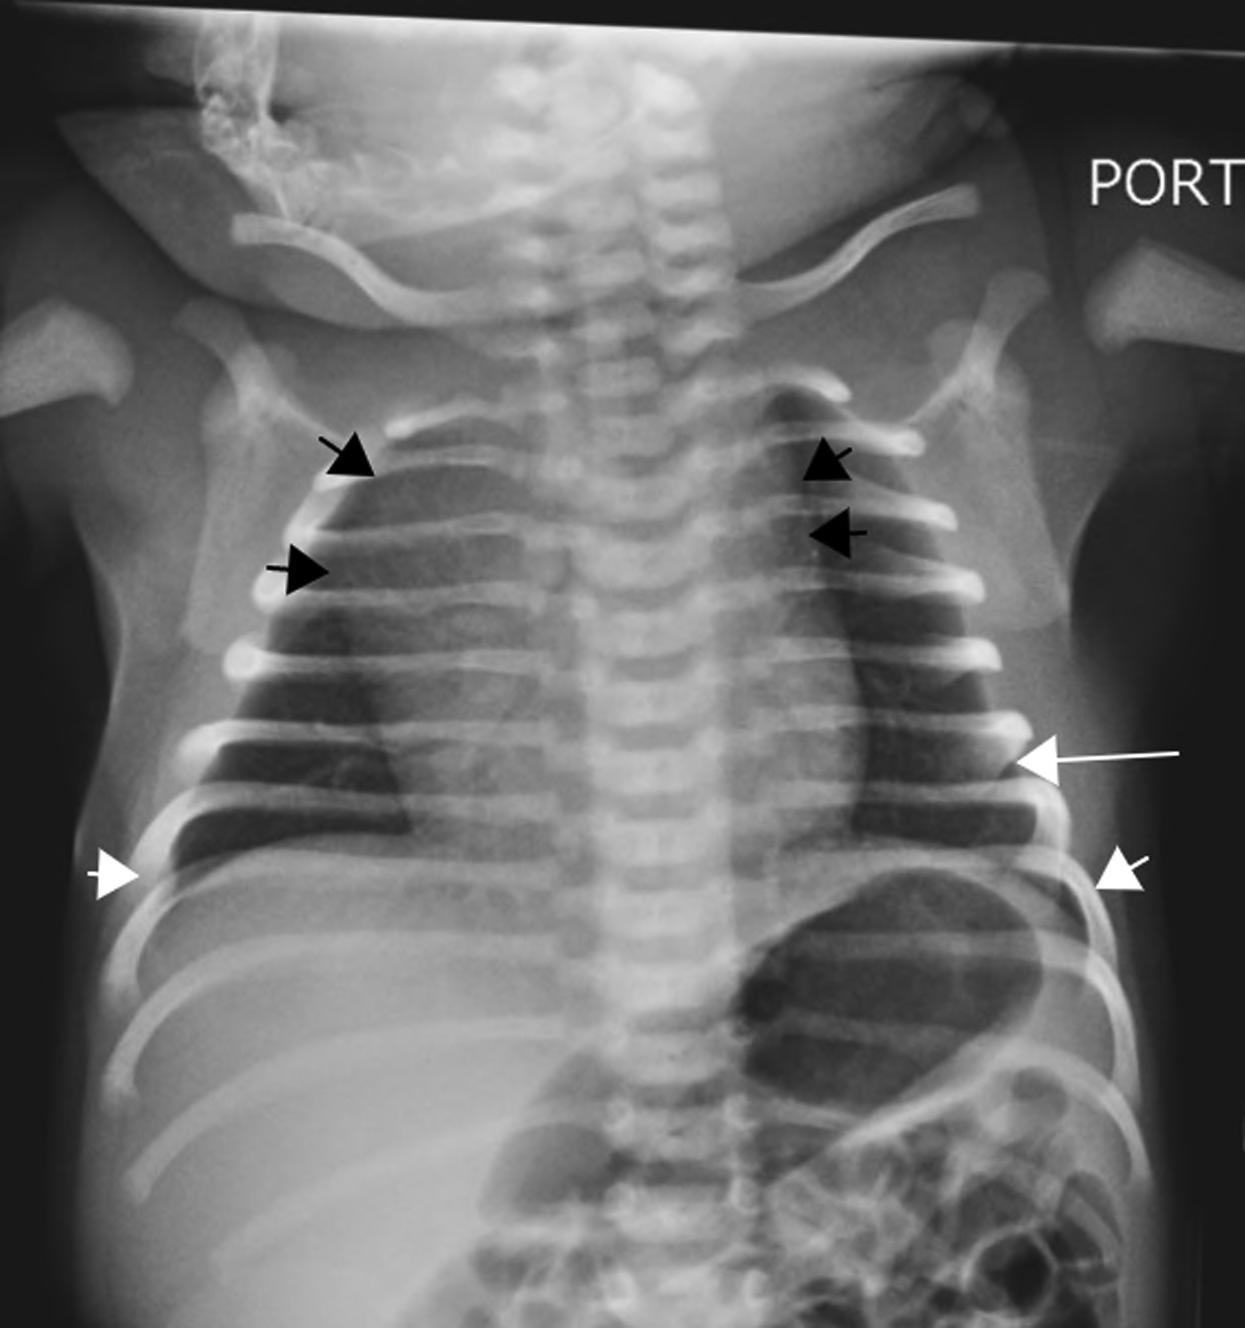

The clinicians for this patient started with a chest radiograph. The initial chest radiographic identified small pleural effusions and interlobular septal thickening, which were suggestive of interstitial pulmonary edema (see Figures 1.1a and 1.1b). Findings become more apparent when compared with a normal 16-year-old’s chest radiographs (Figures 1.2a and 1.2b). Because of the patient’s vomiting, an abdominal film was also obtained, which demonstrated significant cardiomegaly (see Figure 1.1c), thus leading to the diagnosis of dilated cardiomyopathy and/or pericardial effusion. On the chest radiograph, the reduced lung volumes and elevated hemidiaphragms masked the cardiomegaly, which was more apparent on the better penetrated abdominal radiograph.

FIGURES 1.1 a, 1.1b, 1.1c, AND 1.1d . (a, b) PA and lateral views of the chest demonstrating low lung volumes, pulmonary vascular congestion, interstitial opacities in the lung bases, and bilateral trace pleural fluid; (c) the abdominal radiograph is better penetrated than the chest radiograph, and shows an enlarged cardiac silhouette; and (d) post-procedure chest radiograph showing decreased size of the cardiac silhouette after drainage of the pericardial effusion.